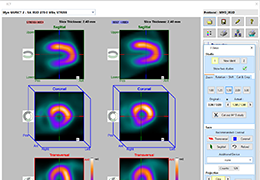

Performs 3D reconstruction and volume rendering.

Multi-planar slicing.

Oblique slicing.

Instant and interactive surface extraction and export to STL and PLY formats.